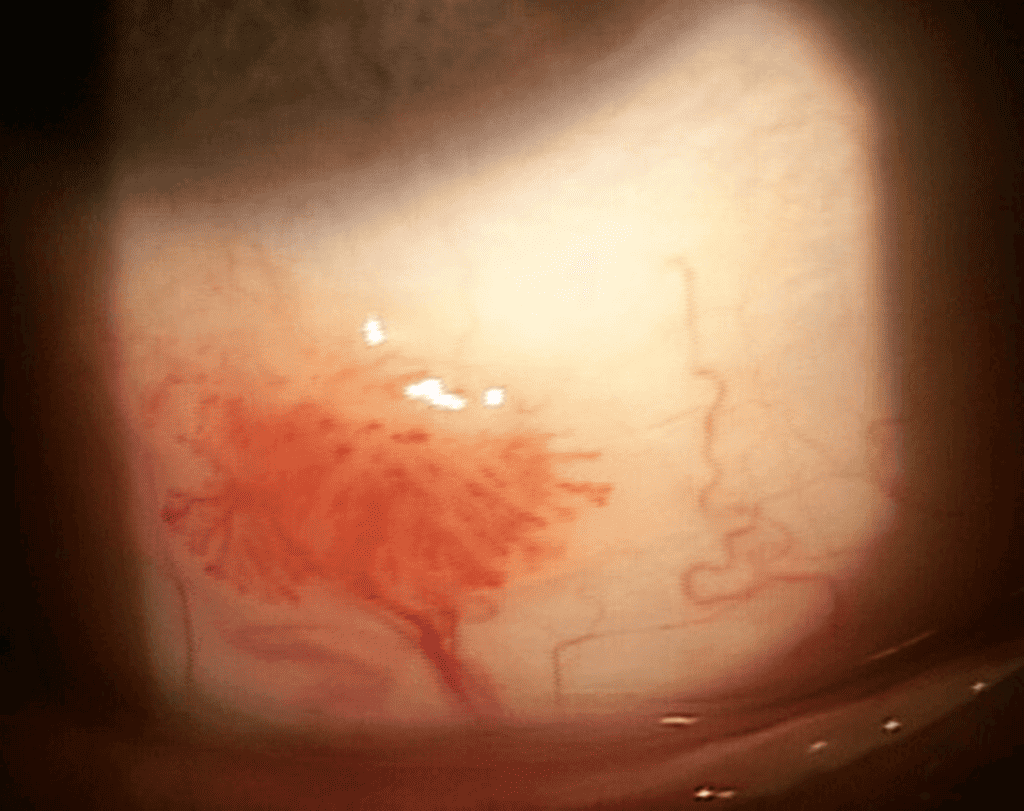

Best-corrected visual acuities were 20/20 in each eye and entrance tests were unremarkable. Anterior segment evaluation revealed clear lids and lashes OD and OS, clear and intact cornea OD and OS, a sessile, gelatinous, immobile, vascularized lesion that measured 4 mm x 3.5 mm on the inferior bulbar conjunctiva without corneal involvement OD (Figure 2), white and quiet bulbar conjunctiva OS, clear and quiet palpebral conjunctiva OD and OS, deep and quiet anterior chamber OD and OS, and flat irides without neovascularization OD and OS. IOP measured 9 mmHg OD and 9 mmHg OS with Goldmann applanation tonometry. Posterior segment evaluation revealed incipient cataracts OD and OS and was otherwise unremarkable.